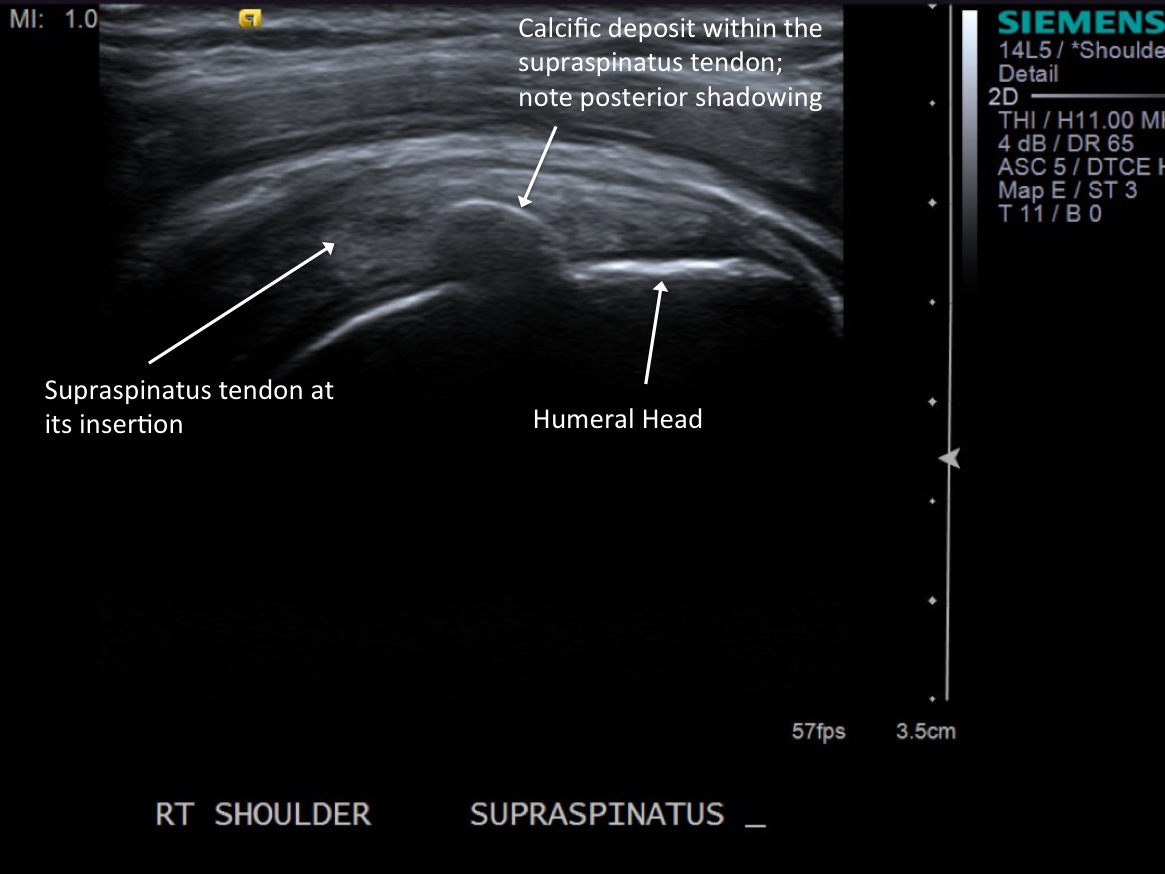

• descriptiondescription

Post procedure scan demonstrating decreased size and decreased central echogenicity of calcific deposit and injectate surrounding it.

12. Exchange the 10cc lidocaine syringe with a 10cc syringe containing normal saline. Repeat the intermittent small injection and aspiration and look for milky aspirate. \

13.Repeat once more with another 10cc syringe containing normal saline.